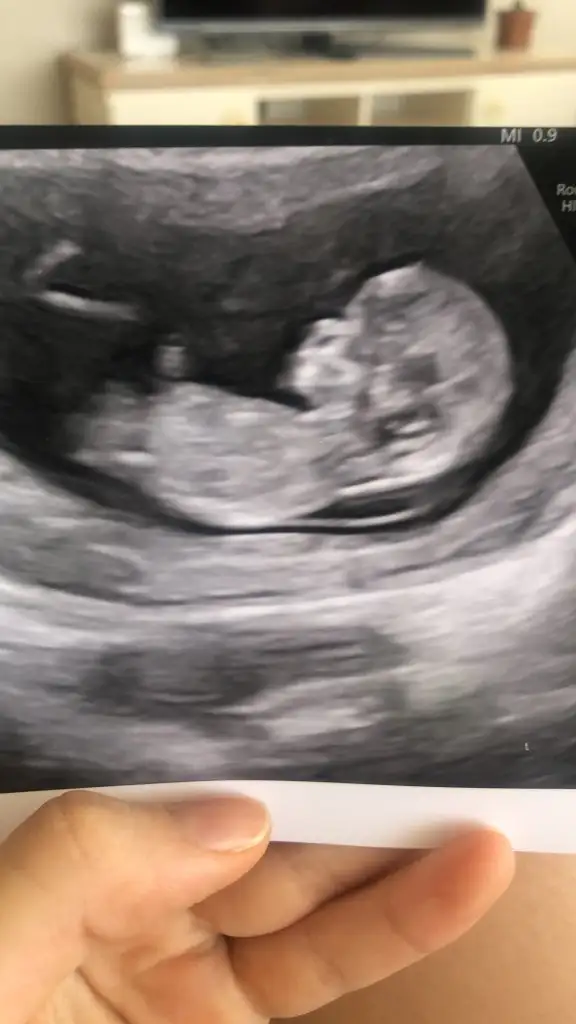

Biz biraz daha büyüdük yorum alabilir miyim rica etsemKafa şekli burada erkek gibi. Nub çok düz değil ama çok dikte değil. Pozisyondan kaynaklanıyor sanırım. Şimdilik erkek diyebilirim. Benim bebeğimle böyle kendini tam belli etmedi sonra bir prenses olduğu belli oldu. Rabbim gönlündekini nasip etsin inşallah hayırlısı ve sağlıkla.

Arada tarif de kaynamışBiz biraz daha büyüdük yorum alabilir miyim rica etsem